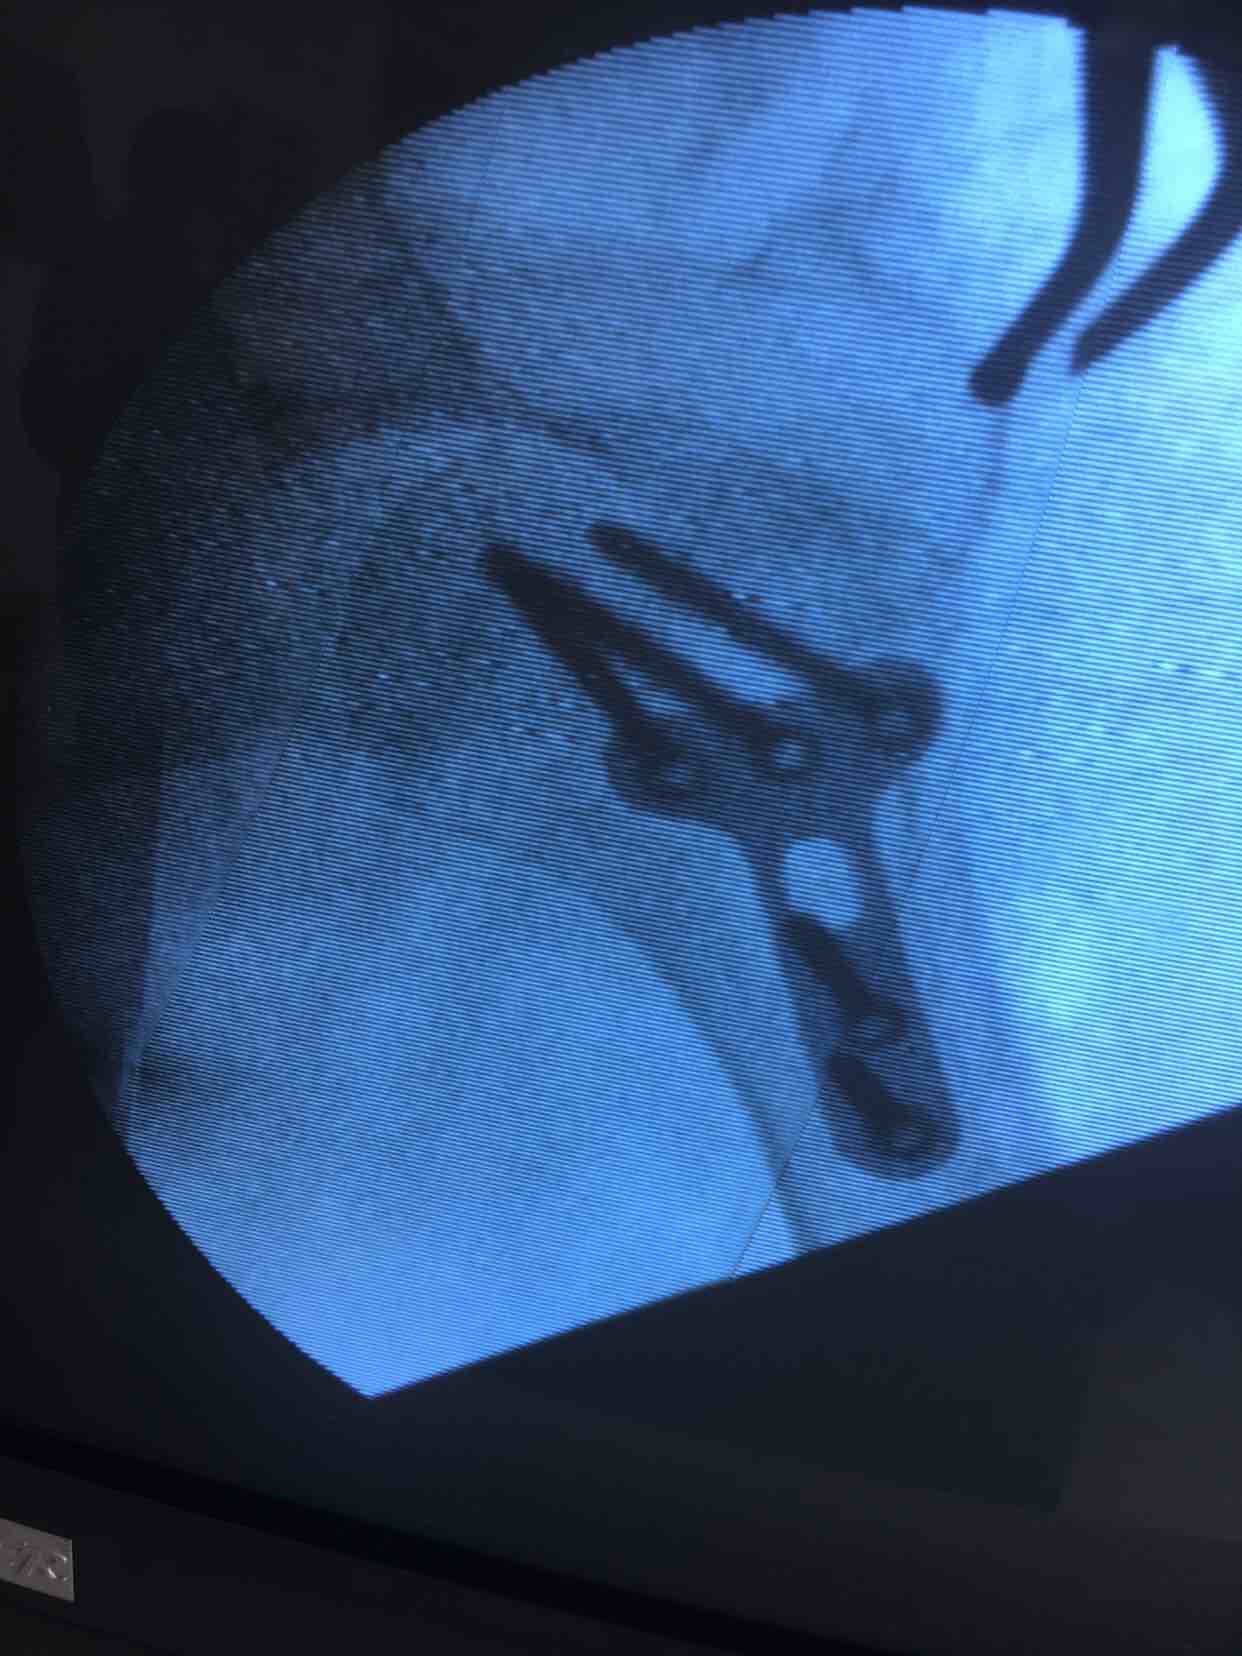

肩关节脱位并大结节骨折(切复内固定)

诊断肩关节脱位并大结节骨折在臂丛麻醉下行切复内固定术,术后外展架固定,抗炎,消肿等处理。